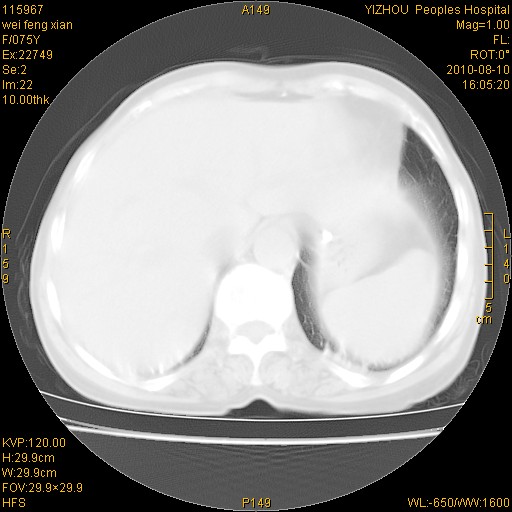

标题: CT28313:两肺弥漫性病变 [打印本页]

标题: CT28313:两肺弥漫性病变

女,75岁,患者反复头昏乏力面色苍白3年,再发10天入院。临床贫血查因。

双肺间质增生并右肺上叶炎性改变,不除外右肺上叶结核病肺内播散

考虑右肺上叶炎症合并双肺结核可能性大,建议上传纵隔窗ct图片。

双肺结核可能性大

考虑尘肺并结核;右上肺支气管扩张!

结核、尘肺、支气管肺泡癌都不能除外

右肺上叶继发性肺结核伴肺内血型播散!

考虑右肺上叶继发性肺结核伴两肺播散。